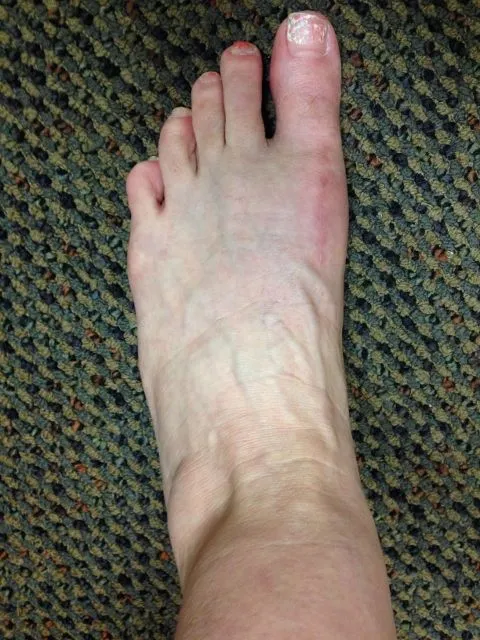

Before and 6 months status post bunionectomy.

1 year postop